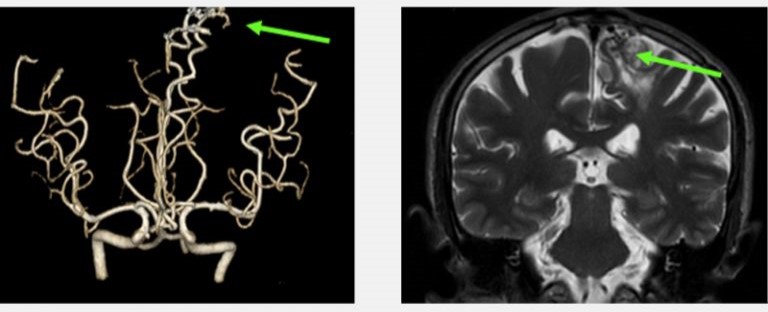

再者,比喻說我們人體就如一部汽車,政府規定汽車每一年都要例行檢查汽車的零件,看看是否安全行駛,不會在駕駛中失去安全操作而發生意外。然而,抽血檢查就像放取汽車偈油來檢查一樣,不能反影汽車內部零件的耗損和安全性。那麼要防止人體腦中風意外的發生, 就是不能單單透過抽血檢驗,而是要利用三維立體腦血管造影,作出詳盡的人體零部件篩查。如果例行的身體檢查包括了三維立體腦血管造影,腦神經外科醫生就可以在患者沒有症狀之前,找出先天性或後天性的計時炸彈,在其未爆發前將其拆除,來避免中風。

先天性的大腦動靜脈畸形血管瘤(Congenital Cerebral Arteriovenous Malformation)

一般人亦以為中風和年齡一定有關係,然而這是錯誤的,任何年齡即使是小孩也有機會中風。皆因中風是腦血管疾病所致,而我們每人無論任何年紀也有機會患上先天、或後天的腦血管疾病。小孩和少年的中風,可以是患有先天性的大腦動靜脈畸形血管 (Congenital Cerebral Arteriovenous Malformation) 所導致的出血性中風。

兩位分別是16歲的少年和56歲的男士,在沒有任何徵象之下做了詳盡的身體檢查,三維立體腦血管造影顯示兩人的大腦都有先天性的腦血管動靜脈畸形,在專科醫生建議之下透過了一段時間的觀察和保守治療,其後利用了微創內血管治療加上放射治療,畸形血管得到了有效的根治,病人與生俱來的大腦炸彈得到了拆除,減低了他們將來出血性中風的可能性。